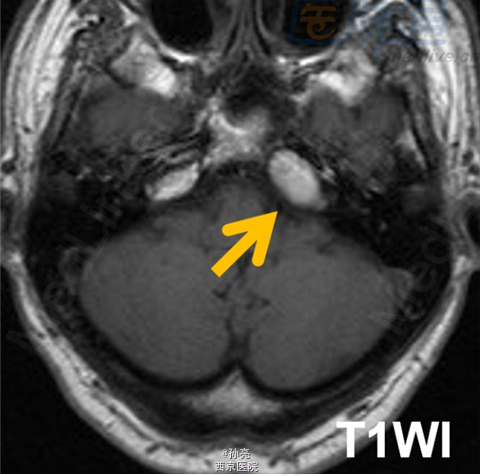

50岁男性,长期左侧耳聋。

CT检查多表现为颞骨岩尖部出现边界清楚的囊性膨胀性病变(图A箭头)。由于包块内血液分解产物和蛋白质碎片的积累,其在MRI检查时,多表现为T1和T2加权图像上的高信号影(图B箭头)。在MRI的T2加权图像上,可见到包块的周围有明显的低信号影包绕。而这主要是由含铁血黄素在局部的沉积所致(图C箭头)。此外,包块多无扩散受限(图D箭头)。